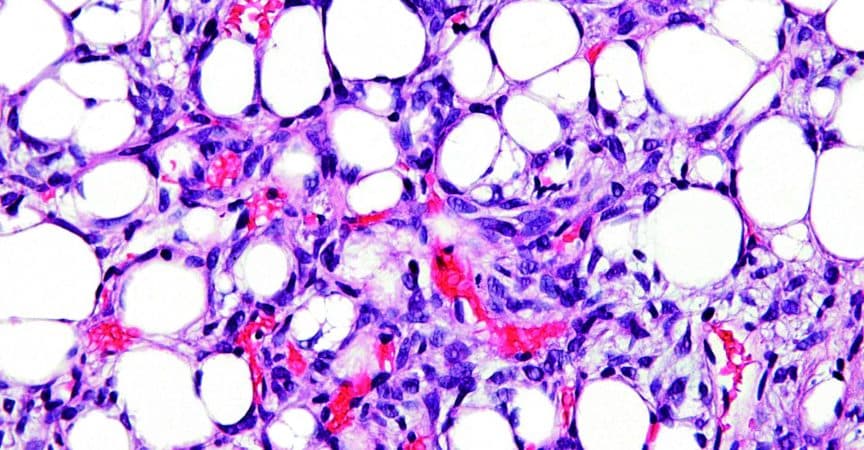

Für die Polymyalgia rheumatica typische Veränderungen wie eine Koxitis oder Bursitis trochanterica fehlten jedoch. Stattdessen zeigte die bildgebende Diagnostik (MRT, CT) eine malignitätsverdächtige lipomatöse Raumforderung im Unterbauch, die bereits die intrapelvinen und -abdominalen Organe verdrängt hatte. Der Tumor wurde operativ entfernt und erwies sich in der Histologie als hochdifferenziertes Liposarkom. Auf eine anschliessende Chemo- und Strahlentherapie verzichtete man.